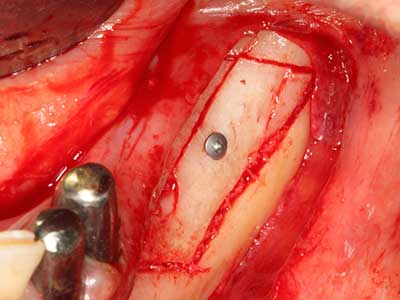

Si es preciso realizar intervenciones quirúrgicas en las que el hueso está en contacto directo con estructuras sensibles, como son los vasos sanguíneos o los nervios, los instrumentos rotativos presentan un enorme potencial de provocar lesiones iatrogénicas. Así, precisamente en la representación de nervios después de una lesión iatrogénica, o en el transcurso de la lateralización de un nervio para resecciones, reconstrucciones o incorporación de implantes, los equipos piezoeléctricos pueden resultar muy útiles para preparar la tapa ósea y retirar las partes de tejido duro cercanas al nervio (fig. 17-20). Por lo general, un ligero contacto del cordón nervioso con el inserto piezoeléctrico no tiene consecuencia alguna; ahora bien, un procedimiento poco cuidadoso con movimientos tipo sierra o piezas de trabajo sobre la base ósea aún existente puede provocar lesiones nerviosas temporales o incluso permanentes. Con todo, el riesgo de sufrir una lesión de este tipo se considera significativamente inferior que en los casos en los que se utilizan sierras y fresas (Pereira, Gealh et al. 2014).

Fig. 17: Tomografía computarizada de un osteoma de crecimiento progresivo ...

Fig. 17b: justo al lado del canal alveolar con irritación nerviosa (vista lateral y coronal).

Fig. 18: Preparación de una tapa cortical con la sierra ósea piezoeléctrica (Piezomed, W&H).

Fig. 19: Zona operada después de neurolisis y eliminación del osteomo.

Fig. 20: La tapa ósea extraída se readapta y se fija mediante un tornillo para osteosíntesis (KLS Martin, Tuttlingen).